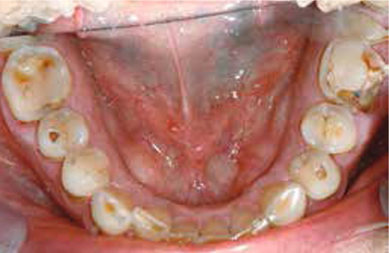

Afb. 4

Occlusaal aanzicht van de onderkaak.

Bij het extraoraal onderzoek zie ik een lichte hypertrofie van de m. masseter. Intraoraal tref ik een ernstig versleten dentitie aan waarbij de slijtage niet passend bij de leeftijd kan worden genoemd (afbeelding 2-7 en tabel 1) .